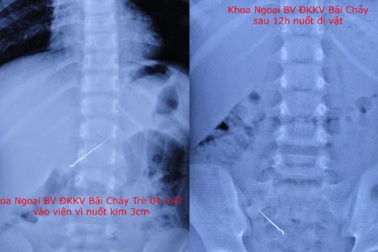

Bé 4 tuổi nuốt kim dài 3cmMột bé gái 4 tuổi ở Hoành Bồ (Quảng Ninh) đã nuốt kim 3cm vào bụng. Sau nuốt khoảng 2 tiếng, bố mẹ em thấy con đau bụng, vội đưa đến bệnh viện Đa khoa khu vực Bãi Cháy cấp cứu.